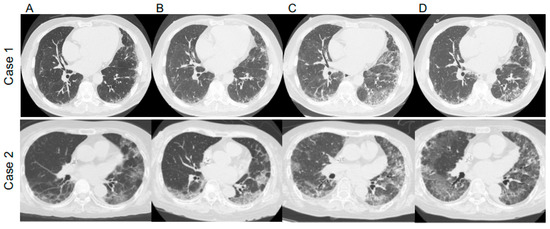

2.1. Case 1

2.2. Case 2